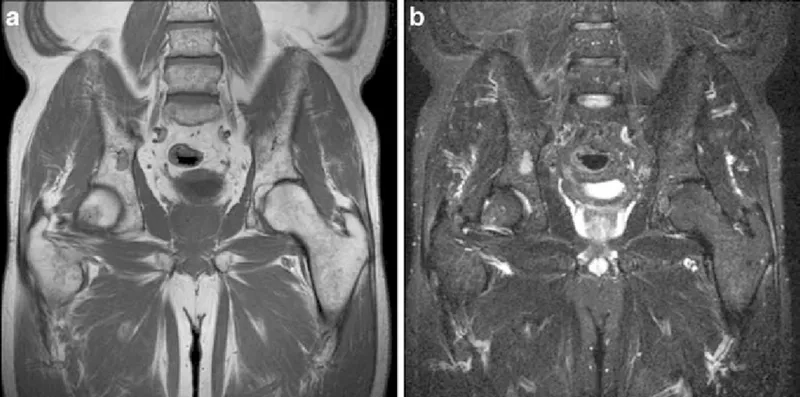

Image of the disease Multiple Myeloma